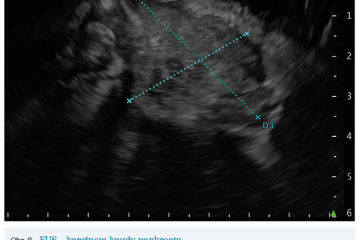

EUS umožňuje přesné vyšetření pankreatu. Lze také identifikovat a vyšetřit regionální lymfatické uzliny a vztah pankreatických lézí k okolním cévním strukturám. EUS může také sloužit jako navigace k odběru bioptického materiálu k cytologickému a histologickému vyšetření.21 AI je zde využívána k potvrzení malignity v IPMN. Kuwahara a kol. dosáhli s využitím 3 970 snímků a CNN algoritmu velké úspěšnosti v diferenciaci benigní a maligní IPMN s AUC 0,98.22 Řada studií se již zabývala AI asistovaným rozlišením chronické pankreatitidy a karcinomu pankreatu s AUC 0,940–0,986.23,24 Velká studie obsahující 1 174 461 snímků z celkem 583 případů hodnotící rozlišení autoimunitní pankreatitidy, karcinomu pankreatu, chronické pankreatitidy a normálního pankreatu dosáhla pro karcinom pankreatu AUC 0,97625 (obr. 6–9).